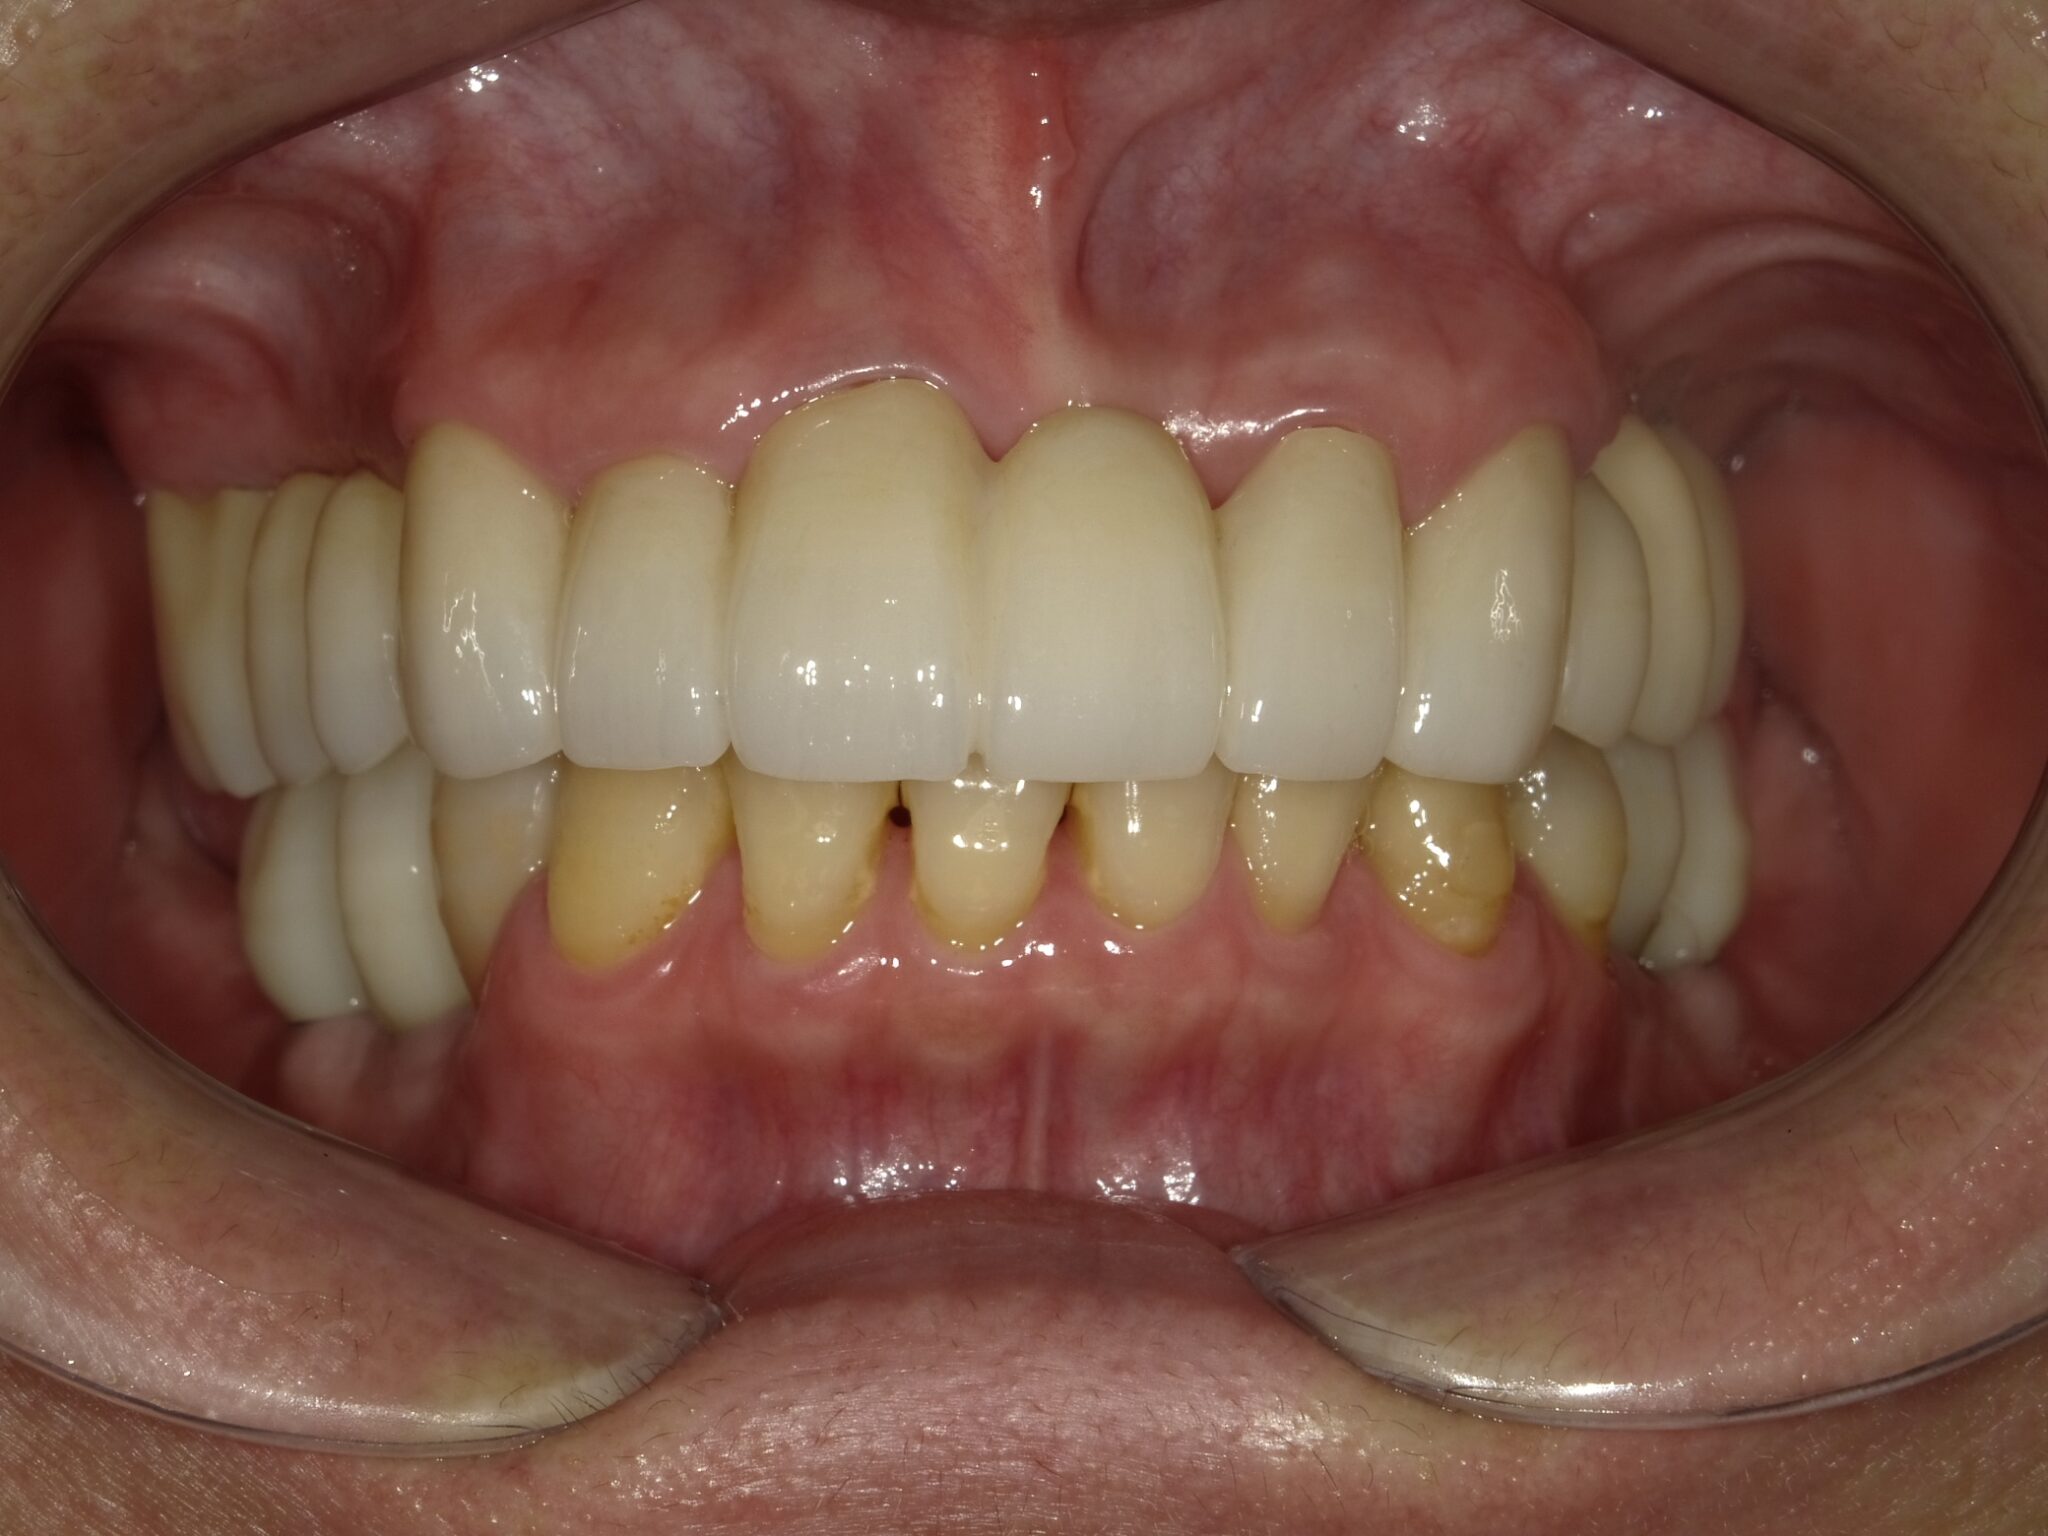

全顎治療症例

| 主訴 | 全体的に見た目を綺麗にしたい。奥歯でしっかり噛みたい。 |

| 治療内容 | インプラント埋入(左下5・6,右下5・6,左上4・6) サイナスリフト(左上4・6) ジルコニアBr(右上6−左上3) E –MAX CAD(右下4) セラミックインレー(左下4) |